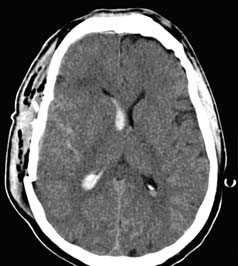

г) Травматическое субарахноидальное кровоизлияние. Субарахноидальное кровоизлияние (САК) — скопление крови между паутинной и мягкой мозговой оболочками головного мозга. САК развивается в большинстве случаев травмы головы от средней до тяжелой степени тяжести как наиболее частой причины.

Ключевые данные визуализации:

- Гиперденсный сигнал в бороздах конвекситальной поверхности головного мозга или (реже) в спинномозговой жидкости цистерн основания головного мозга.

- Обязательно осмотреть межножковую цистерну и затылочные рога.

- Наличие в непосредственной близости от САК переломов и первичных паренхиматозных повреждений головного мозга, таких как ушибы, вместе с анамнезом травмы и расположением САК помогут при дифференциальной диагностике с аневризмой вызванной САК.

Эпидуральная гематома (слева), которая возникает в результате разрыва оболочечной артерии,

как правило, на фоне перелома кости черепа, представляет собой скопление артериальной крови

между твердой мозговой оболочкой и внутренней поверхностью черепа.

При субдуральной гематоме (справа) разрыв мостиковых вен между головным мозгом

и верхним сагиттальным синусом приводит к скоплению крови между паутинной и твердой мозговыми оболочками.